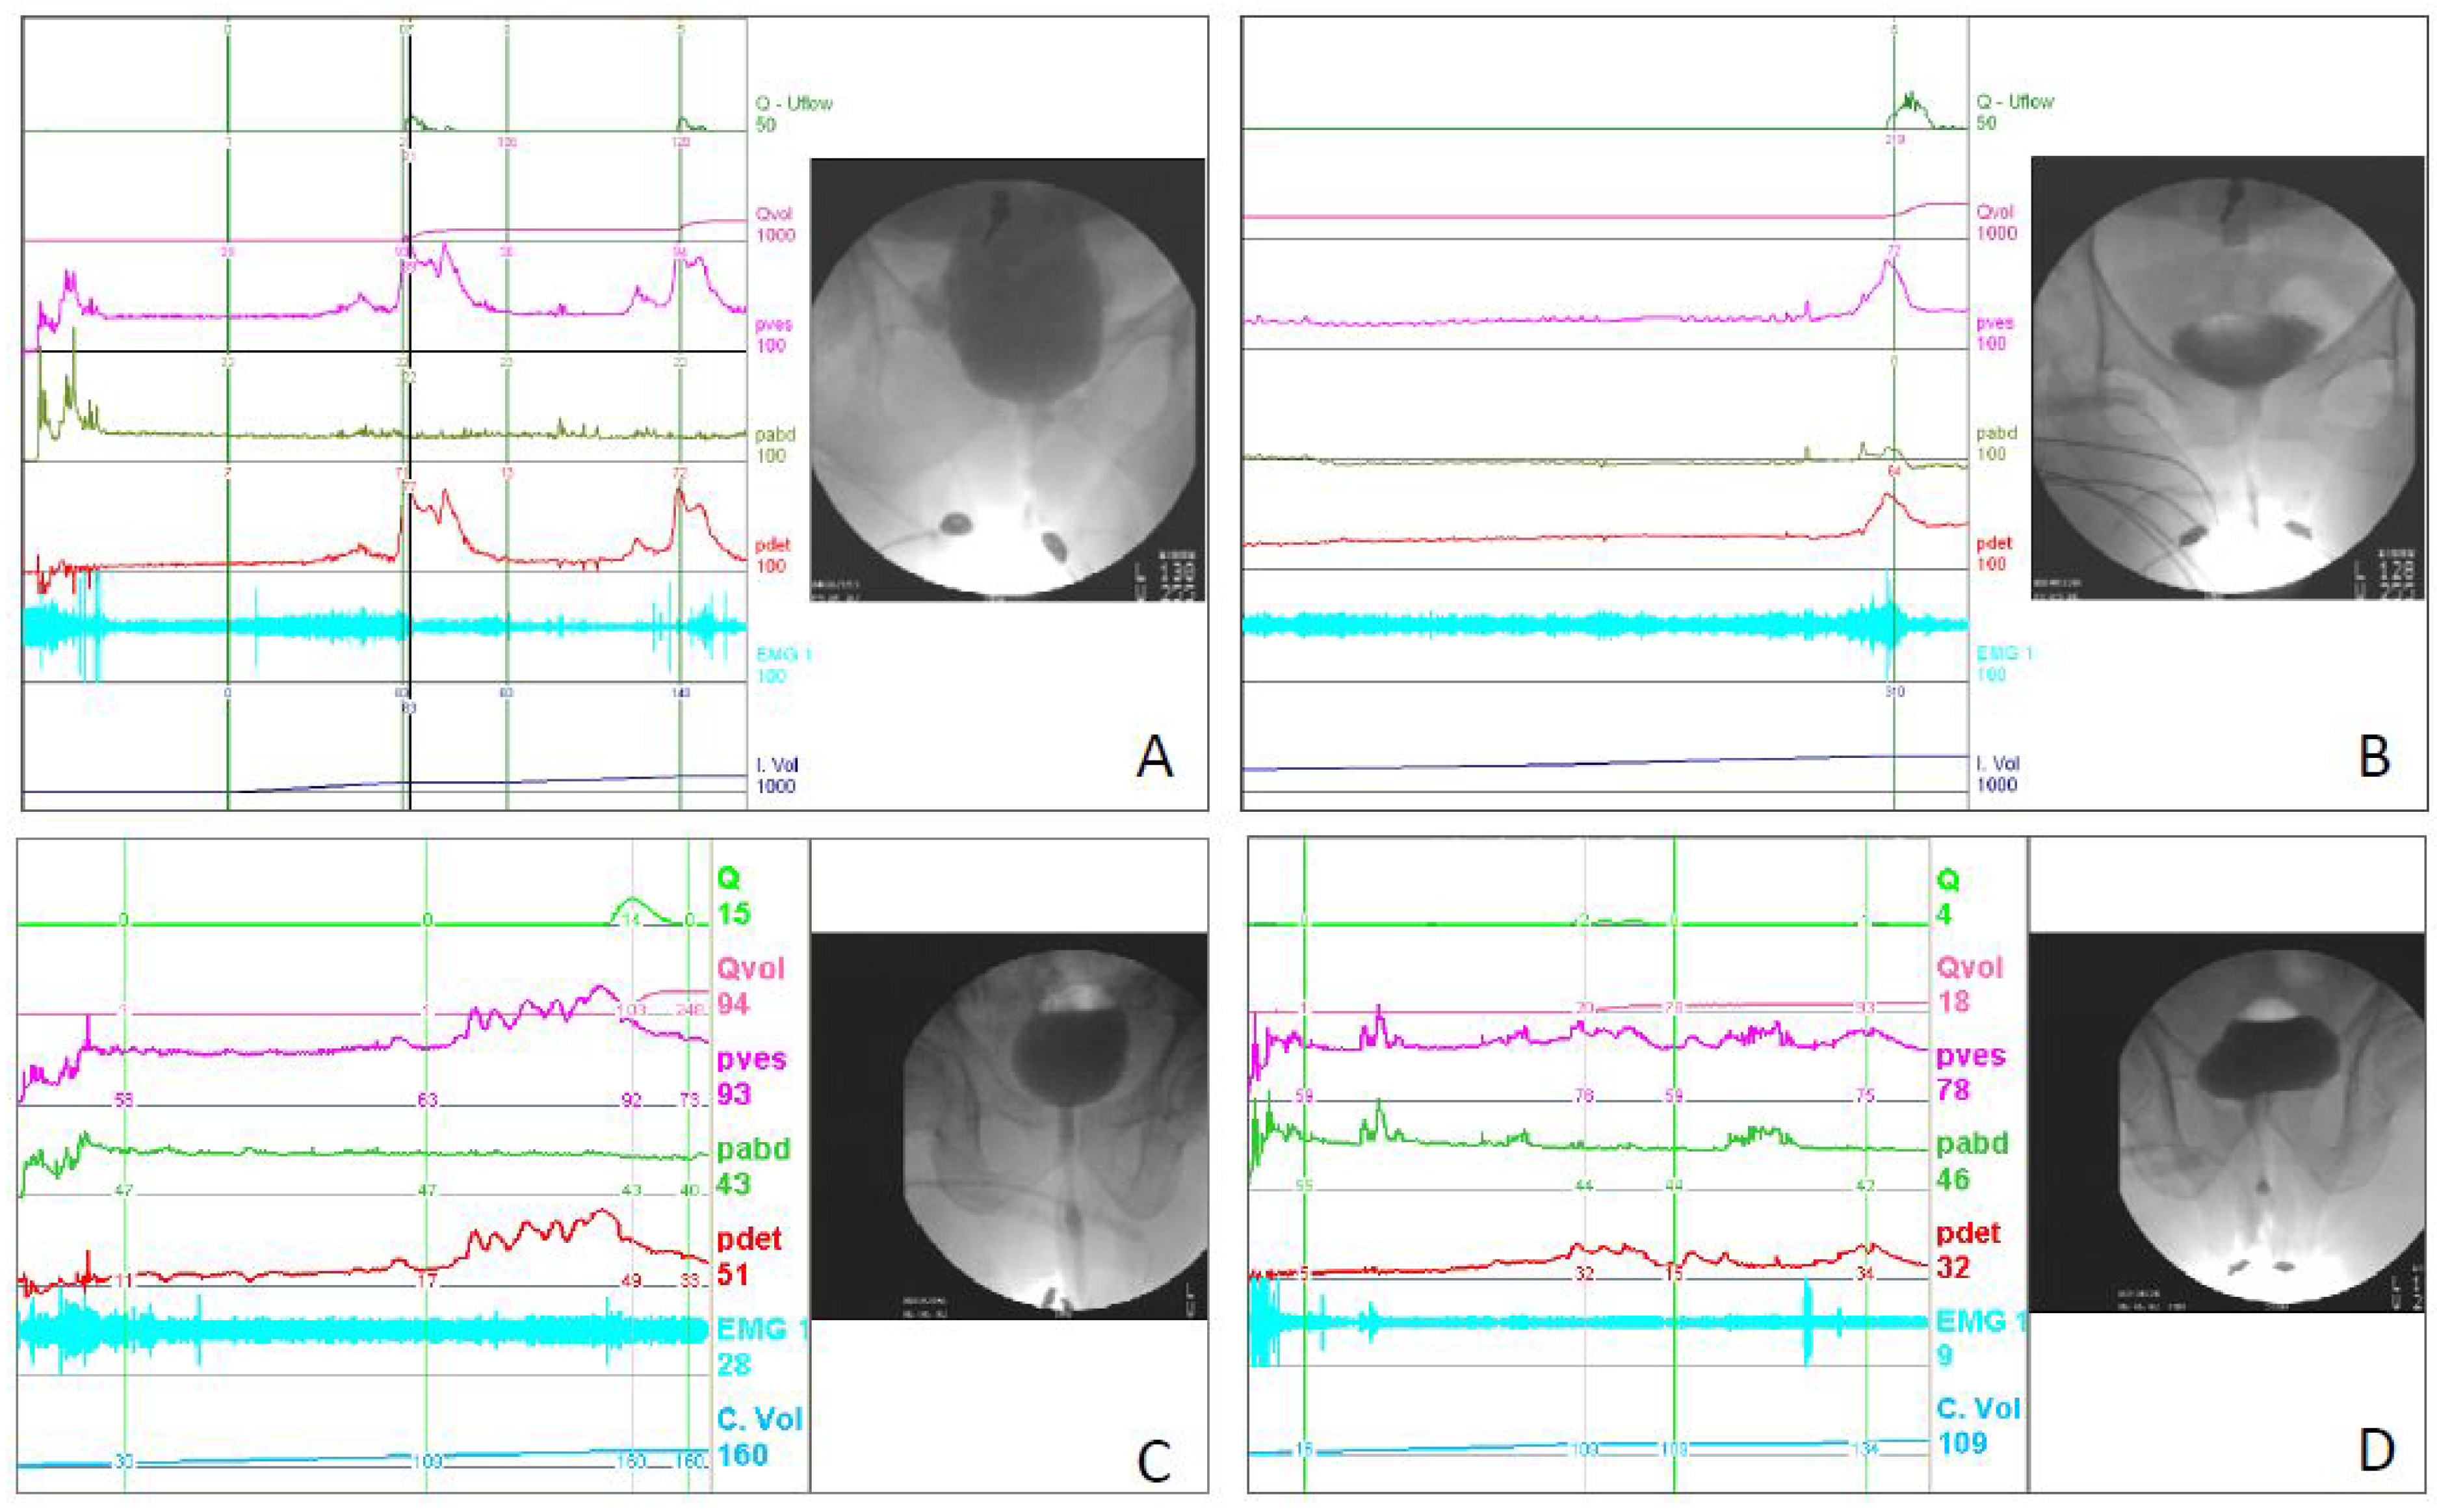

3. Videourodynamic Study